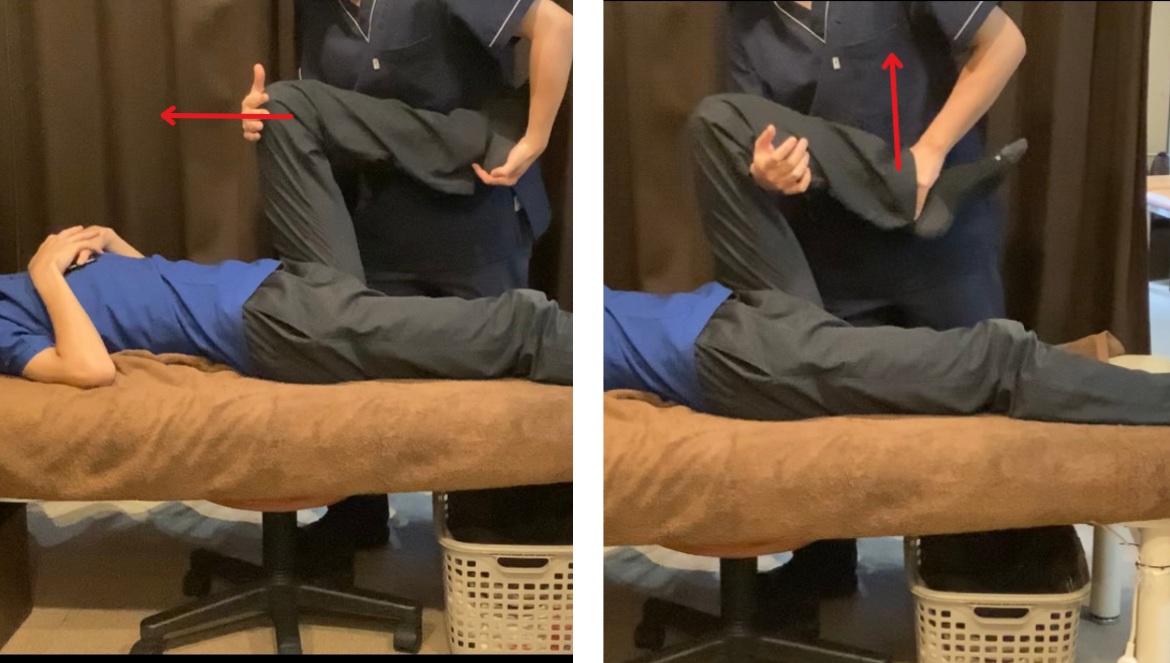

▶ 動作チェック

・ストレッチ時の違和感や可動域の確認

・力を入れたときの痛み